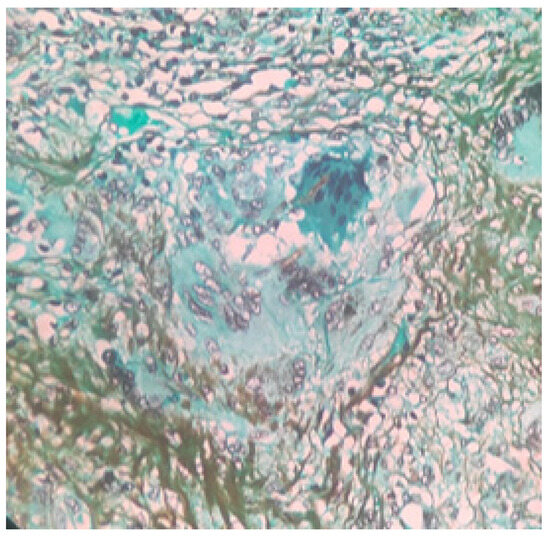

2. Case Presentation